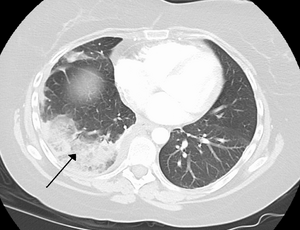

الرضة الرئوية هي كدمة ناجمة عن صدمة في الصدر. وتؤدي إلى نزيف في الحويصلات الهوائية مما يتسبب في تراكم السوائل مما قد يعيق التنفس، وقد يكون هذا إما خفيفاً أو شديداً. قد تتأثر وظيفة الرئتين أيضاً بالضغط الناجم عن سوائل الانصباب الجنبي في التجويف الجنبي، أو مواد أخرى مثل الهواء (استرواح الصدر)، أو الدم (تدمي الصدر)، أو أسباب نادرة. يمكن فحص هذه الحالات باستخدام أشعة الصدر السينية أو التصوير المقطعي المحوسب، وقد تتطلب إدخال أنبوب تصريف جراحي لتحديد السبب الأساسي وعلاجه.[74]